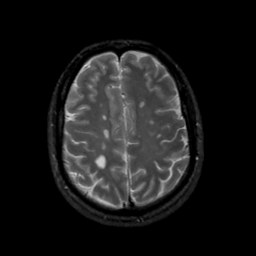

MR Study #16, June 23, 1991 -- Slice #37

[Home][Help][Clinical][Tour 1][Tour 2] Slice 37